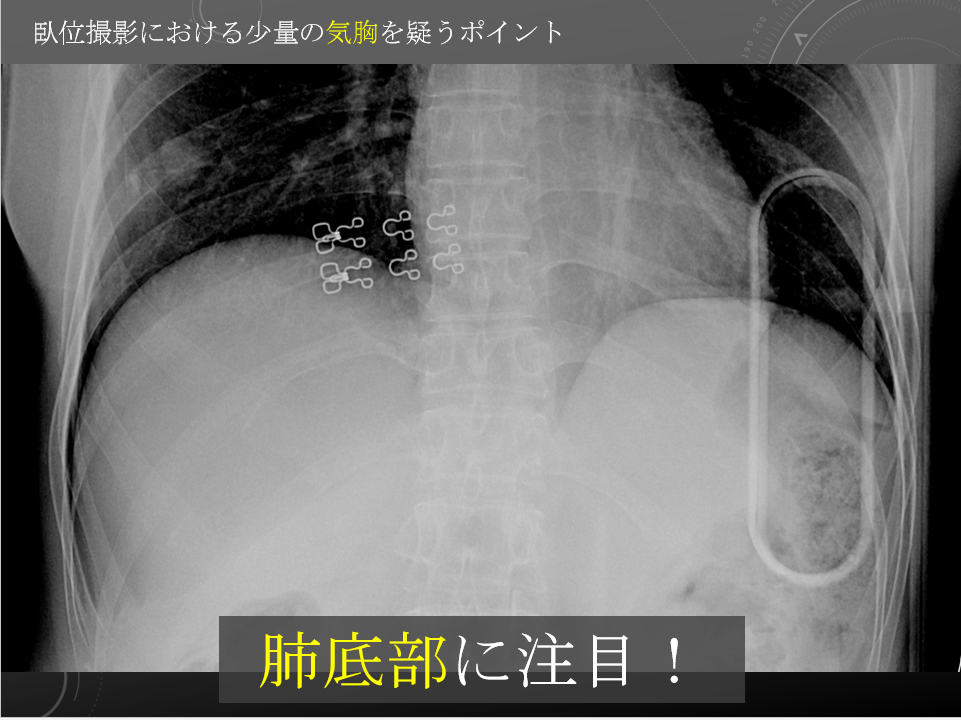

61F 交通外傷 オートバイ×歩行者 歩行者

歩行者

オートバイ 30-40km/hr 接触後約6m引きずられた

胸部臥位単純写真

右気胸が認められます。

右気胸、右多発肋骨骨折、右鎖骨骨折。

61F 交通外傷 オートバイ×歩行者 歩行者

歩行者

オートバイ 30-40km/hr 接触後約6m引きずられた

胸部臥位単純写真

右気胸が認められます。

右気胸、右多発肋骨骨折、右鎖骨骨折。

高エネルギー外傷精査

歩行者 vs 原付バイクの交通外傷 搬送後舌根沈下あり、気管挿管された。

右第4-7肋骨腹側~外側の骨折が認められ(図4)、右気胸を伴っています(図5)。縦隔は軽度左方へ偏位していますが、緊張性気胸を強く示唆するほどの所見でありません。大量胸水貯留は伴っていません。右肺中下葉の末梢よりに不整形なすりガラス病変が認められ、肺損傷が示唆されます(図5)。

右多発肋骨骨折および右気胸:緊張性気胸の所見や、大量胸水貯留は伴っていません。